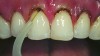

A 55-year-old woman presented with root decay along the left lateral incisor (tooth No. 10) and canine (tooth No. 11) (Figure 1). It was proposed that invisible Class V restorations be placed using an MMID procedure. There are several keys to attaining a successful invisible Class V restoration. Proper understanding of composite resin shade selection, preparation design, and sequence of composite resin layering are important to achieve an ideal blending of the composite resin to the existing tooth. Correct finishing and polishing technique is equally essential in obtaining a seamless esthetic restoration.3,11

Shade selection is always completed before initiating treatment; this is important to develop the proper shade-layering sequence. Composite shades were placed directly on the tooth and shades that matched the areas of the tooth being restored were chosen (Figure 2). To achieve an invisible Class V restoration, a more complex layering process is needed to blend the composite resin.

CASE 1 INITIAL RESTORATION STEPS (1.) Extensive root decay along teeth No. 10 and No. 11. (2.) Composite resin try-in was done to develop final layering sequence. (3.) Teeth were isolated and minimally invasive preparations were completed with minimally invasive burs. (4.) After a thin liner of resin-modified glass ionomer was placed, dentinal adhesive was bonded to the root in preparation for composite placement. (5.) To match the chromaticity along the gingival aspect, an opacious dentin shade (AO2) was bonded over the resin-modified glass ionomer to mimic the lost dentin.